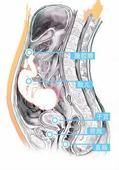

3.B型超音波檢查

可見子宮增大,宮腔內出現彌散分布的雜亂光點反射,但無妊娠囊光環。腹腔內可見胎兒及胎盤反射波。但有時,除子宮和胎頭外,其他結構不易辨認。X線檢查顯示:胎兒影像清晰度增加,而胎兒周圍的子宮軟組織陰影消失;胎兒貼近母體腹壁,位置較高,胎位異常多見。